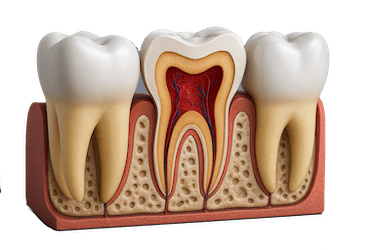

¿Qué es una endodoncia?

La endodoncia es la especialidad odontológica para eliminar la pulpa del diente y sellar el conducto pulpar.

La pulpa, es lo que llamamos nervio, un tejido blando que hay dentro del diente que contiene los nervios y vasos sanguíneos.

Por lo tanto, podemos decir que es un tratamiento de la odontología conservadora que se realiza para eliminar el nervio de la pieza dental y poder conservar así el diente natural del paciente.